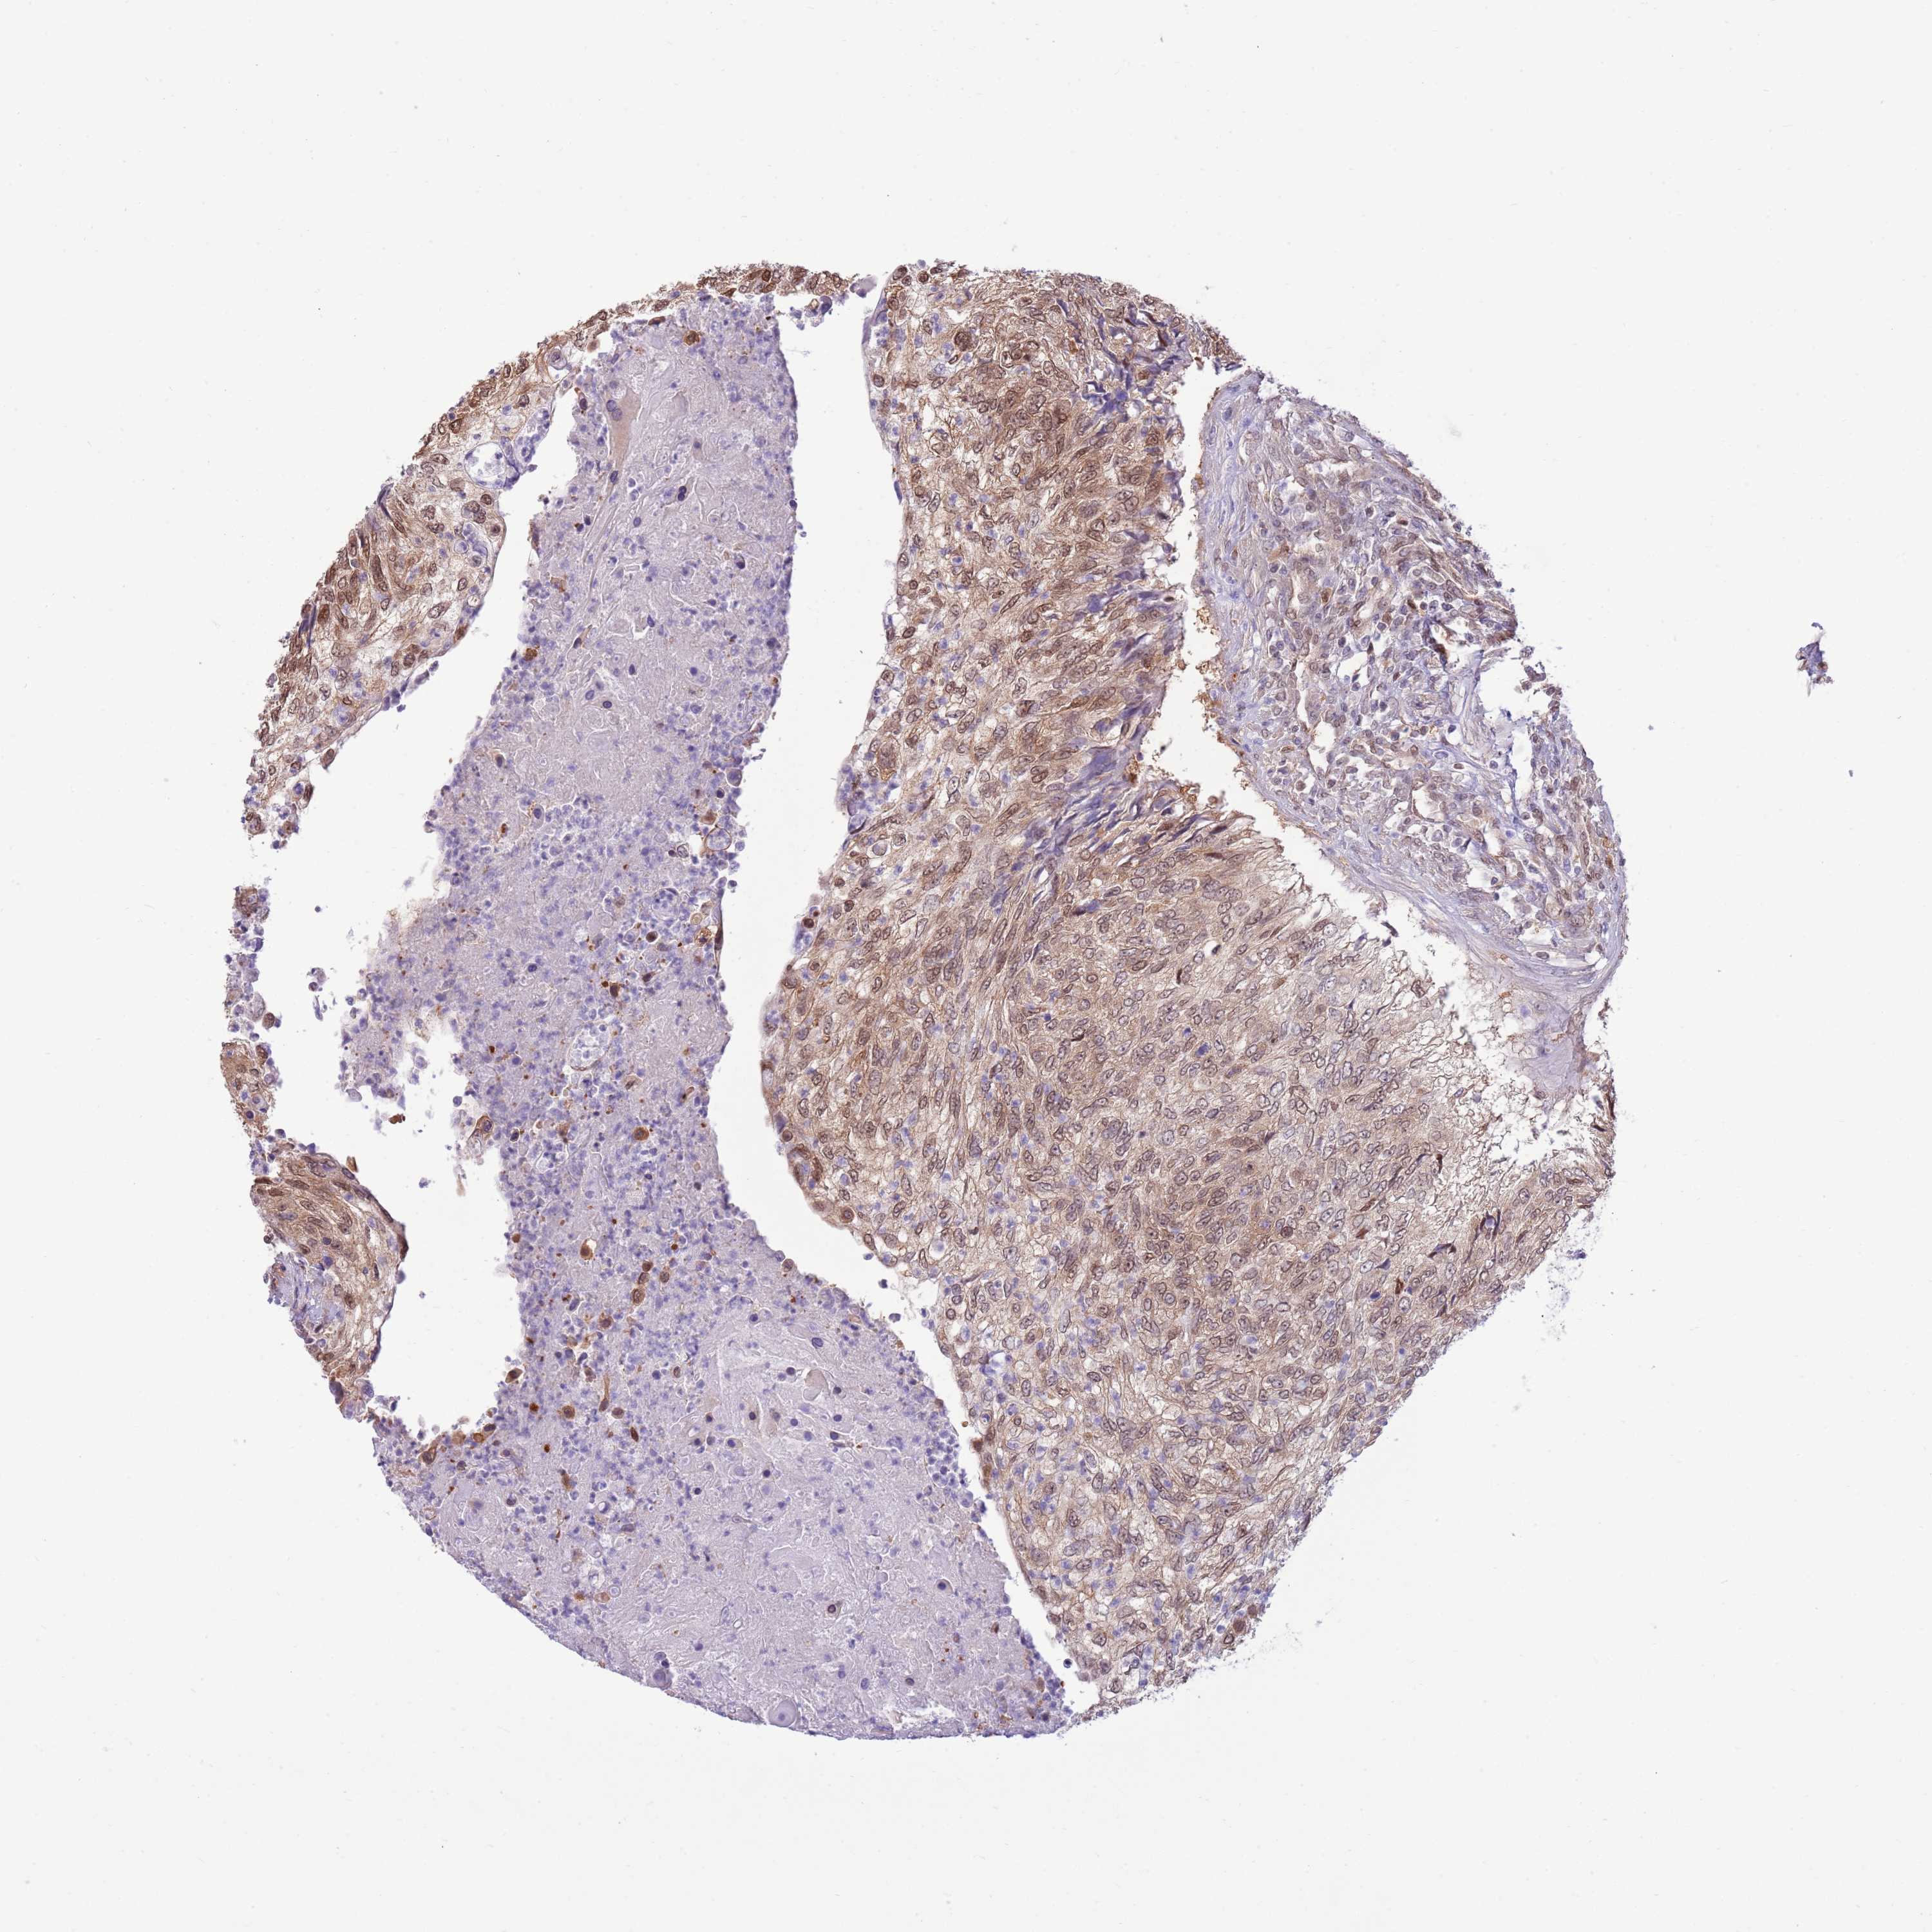

UROTHELIAL CANCER - Protein expressioni

A mouse-over function shows sample information and annotation data. Click on an image to view it in a full screen mode. Samples can be filtered based on level of antibody staining by selecting one or several of the following categories: high, medium, low and not detected. The assay and annotation is described here.

Antibody stainingi

Antibody staining in the annotated cell types in the current human tissue is reported as not detected, low, medium, or high, based on conventional immunohistochemistry profiling in selected tissues. This score is based on the combination of the staining intensity and fraction of stained cells.

Each image is clickable and will lead to virtual microscopy that enables deeper exploration of all samples and also displays staining intensity scores, fraction scores and subcellular localization as well as patient and tissue information for each sample.

Antibody HPA047108

Antibody HPA050628

Staining

High

Medium

Low

Not detected

Intensity

Strong

Moderate

Weak

Negative

Quantity

>75%

75%-25%

<25%

None

Location

Nuclear

Cytoplasmic/membranous

Cytoplasmic/membranous,nuclear

Urothelial carcinoma, Low grade

Urothelial carcinoma, High grade

Urothelial carcinoma, NOS